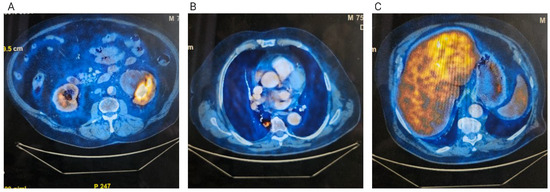

Case Report

Triple Synchronous Primary Malignant Tumors of the Liver, Kidney, and Lung in a Male Patient: Case Report and Systematic Review

by Alexandru Vlad Oprița, Eduard Achim, Cornelia Nițipir, Nicolae Boleac, Alissia-Nicoleta Pilatec and Florin Andrei Grama

Background: Triple primary malignant tumors (TPMTs) are extremely rare and represent a major diagnostic and therapeutic challenge. Their frequency has increased with advances in cancer detection and longer patient survival. Case presentation: We report the case of a 76-year-old male diagnosed with three [...] Read more.

Background: Triple primary malignant tumors (TPMTs) are extremely rare and represent a major diagnostic and therapeutic challenge. Their frequency has increased with advances in cancer detection and longer patient survival. Case presentation: We report the case of a 76-year-old male diagnosed with three synchronous primary malignancies involving the liver, left kidney, and right lung. Imaging revealed a hepatic mass with arterial enhancement and portal washout, a large left renal mass, and a cavitated pulmonary nodule. Histopathological and immunohistochemical evaluation confirmed three distinct tumors: well-differentiated hepatocellular carcinoma, chromophobe renal cell carcinoma, and invasive non-mucinous lung adenocarcinoma. A multidisciplinary oncology board recommended surgical resection of the liver and kidney lesions and stereotactic body radiotherapy for the lung tumor. The patient underwent hepatectomy and nephrectomy but experienced severe postoperative complications leading to multi-organ failure and death. Results of the systematic review: A systematic search identified 83 relevant cases of triple primary malignancies after full-text eligibility assessment. None of the 159 articles included after primary screening described a synchronous association of primary liver, kidney, and lung cancers. Conclusions: This case highlights the importance of thorough diagnostic assessment and individualized, multidisciplinary management in patients with multiple synchronous malignancies. To our knowledge, this is the first reported case of synchronous hepatocellular carcinoma, chromophobe renal cell carcinoma, and lung adenocarcinoma. Full article

(This article belongs to the Section Clinical Diagnosis and Prognosis)

Show Figures

Figure 1